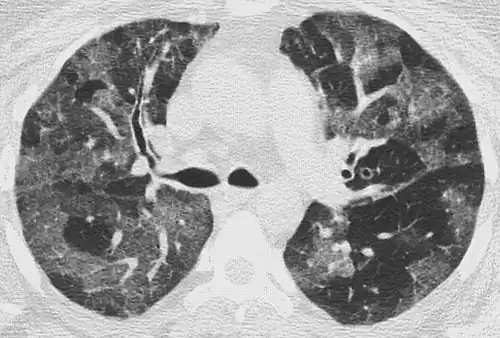

CT image in patient with COVID-19 showing bilateral ground-glass opacities at the periphery of both lungs.

Ground-glass opacity is among the most common imaging findings in patients with confirmed COVID-19.[16][17] One systematic review found that among patients with COVID-19 and abnormal lung findings on CT, greater than 80% had GGOs, with greater than 50% having mixed GGOs and consolidation.[16] GGOs with mixed consolidation has most often been found in elderly populations.[18] Several studies have described a pattern among initial, intermediate, and hospital discharge imaging findings in the disease course of COVID-19. Most commonly, initial CT imaging reveals bilateral GGOs at the periphery of the lungs. During initial stages, this is most often found in the lower lobes, although involvement of the upper lobes and right middle lobe has also been reported early in the disease course.[16][18] This is in contrast to the two similar coronaviruses, SARS and MERS, which more commonly involve only one lung on initial imaging.[19][20] As the COVID-19 infection progresses, GGOs typically become more diffuse and often progress to consolidation.[11][18] This is sometimes accompanied by the development of a crazy paving pattern and interlobular septal thickening.[18] In many cases the most severe pulmonary CT abnormalities occurred within 2 weeks after symptoms began.[17] At this point, many individuals begin showing resolution of consolidation and GGOs as symptoms improve. However, some patients have worsening symptoms and imaging findings, with further increase in septal thickening, GGOs, and consolidation. These patients may develop lung "white-out" with progression to acute respiratory distress syndrome (ARDS) requiring treatment escalation.[17][21]